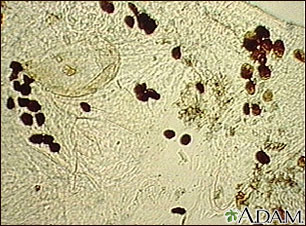

Microfotografía de las heces del ácaro de la escabiosis

Esta es una microfotografía de las heces de los ácaros de la sarna en raspados de piel. Se piensa que este material causa una reacción de tipo alérgico que puede ser responsable de la picazón intensa. Esta picazón puede durar por mucho tiempo después de que los ácaros de la sarna hayan muerto, debido a que los huevos muertos y las heces de dichos ácaros permanecen en la piel.